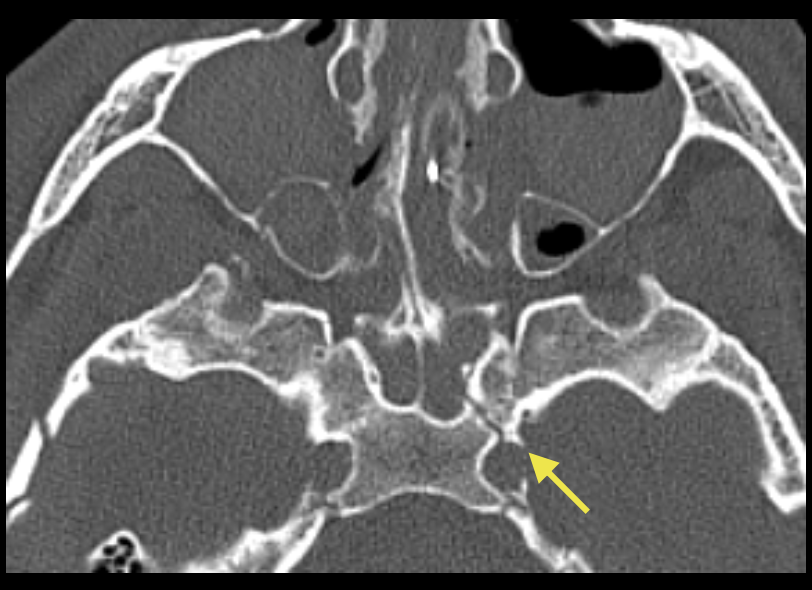

Classification de Markowitz dans les fractures centro-faciale

Évalue l’atteinte du canthus médial

Type I : fragment central entier

Type II : fragment comminutif

Type III : atteinte du ligament palpébral médial (exploration chirurgical)